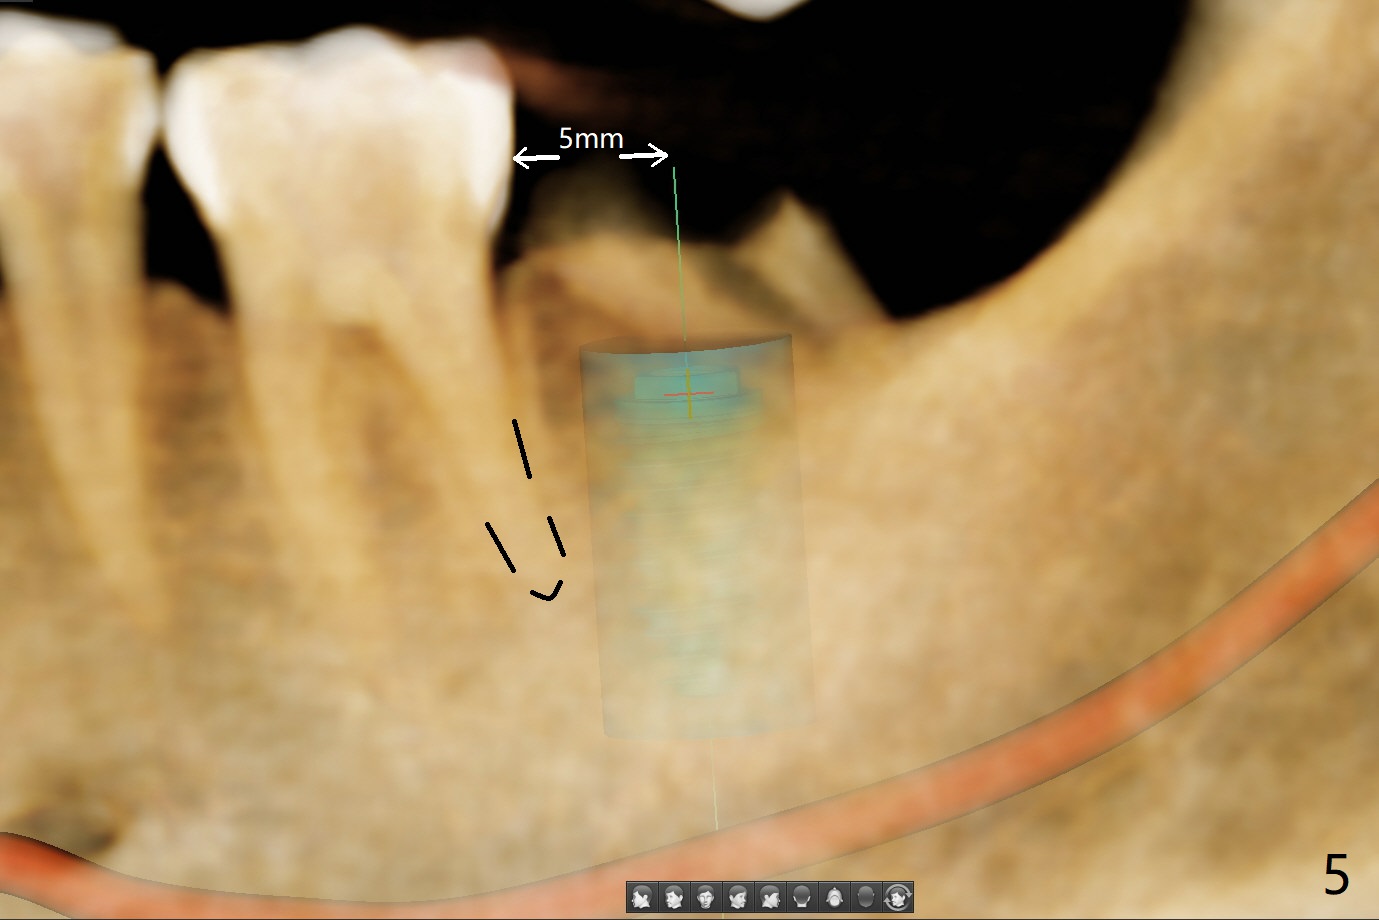

56岁女右侧不好咀嚼,右下7远中龈下龋齿(图一,二),能保留吗?Implant or rct plus crown lengthening, either way is fine, but implant may be more straightforward (Robert). Hi, Jennifer: I love the way you design implant in the mesial slope of the lower 2nd molar (Fig.1,4). When I place an implant free hand, I make sure that the long axis of the implant is 5 mm from the distal surface of the 1st molar (half of the mesiodistal width of the 2nd molar, Fig.5) as long as the implant is not too close to the neighboring root (black dashed line of Fig.5). PAs are taken several times intraoperatively to monitor the distal drifting (Fig.6 open arrow) of the osteotomy (red line). In my opinion, the drifting exists with guided surgery, especially the change of angulation. Can you intentionally move the implant mesially (Fig.7 open arrow) by 0.5-1 mm depending upon bone density or tilt the implant mesial coronally? Thanks for your consideration.